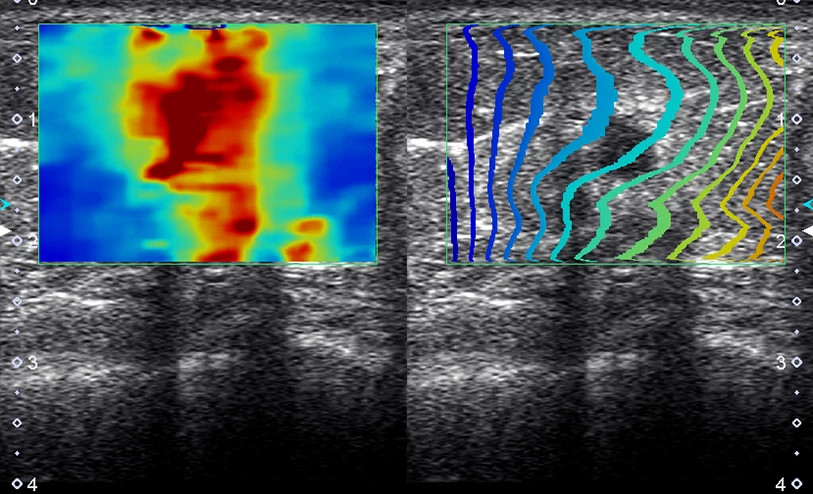

A Canon Shear Wave technológiája kvantitatív és dinamikus vizuális információt nyújt a szöveti merevségről különböző klinikai környezetekben.

Shear Wave Dispersion (SWD) - A viszkozitás elemzése a szöveti merevség mellett

A szöveti merevség változásai gyakoriak a májbetegségekben, azonban a viszkozitás változásainak kimutatása – például a zsíros infiltráció vagy gyulladás miatt – korábban nem volt lehetséges.

A SWE és SWD kombinációja egyszerre nyújt információt a merevségről és a viszkozitásról, így a máj komplexebb értékelését teszi lehetővé.

Gyulladásos folyamatok esetén a májszövet viszkózusabbá válik, és ezeket a változásokat az SWD képes kvantifikálni.